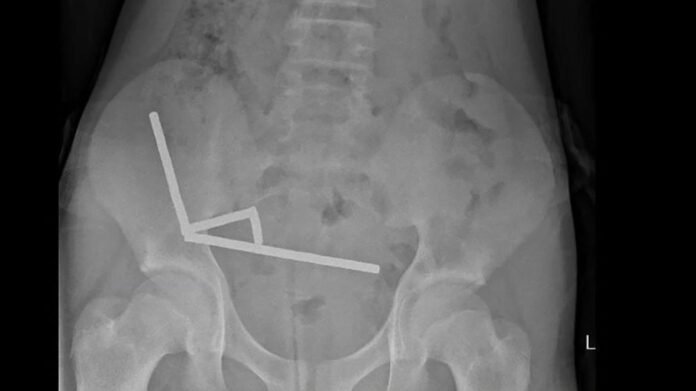

A 13-year-old teenager required extensive surgery after ingesting approximately 100 high-powered magnets that he purchased online. Doctors in New Zealand had to operate on the boy, removing part of his intestines due to severe abdominal pain caused by the magnets forming strips inside his digestive system.

The incident led to the boy enduring significant discomfort for four days before being taken to Tauranga hospital on New Zealand’s North Island. Medical reports indicated that the powerful neodymium magnets, banned in New Zealand since 2013, were acquired from the online marketplace Temu. The magnets had magnetized, forming four long strips that caused tissue death in the boy’s intestines.